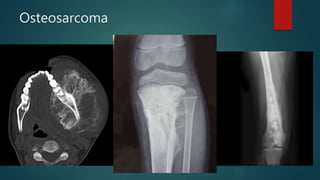

Osteosarcoma

• #99 he distal half of the femur is occupied and expanded with a heterogeneous mass with areas of bone formation. Posterior the periosteum is elevated (Codman's triangle).